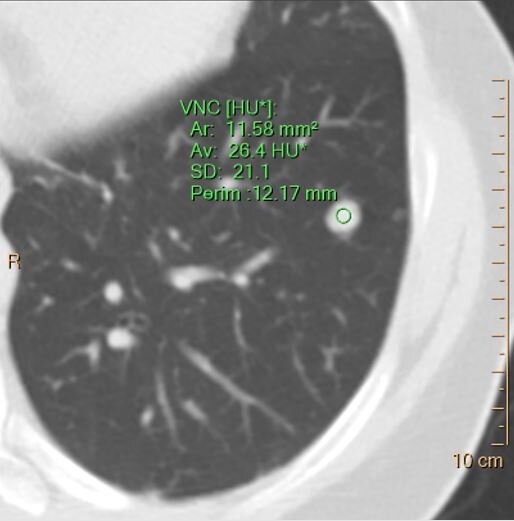

…and about 26 HU on virtual non-contrast. So there is no enhancement.